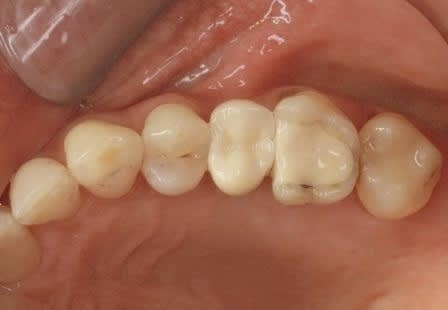

je voulais parler de ce fact pour les implants courts:minimum 4mm os vertical peut suffire (pour eviter un sinus lift externe de tatum) . dans ma pratique depuis quelques années je vois que ca marche , quelques cas cliniques des années passées.

j´ai oublié : 4mm plus 2mm( gagnés par un sinus lift interne)